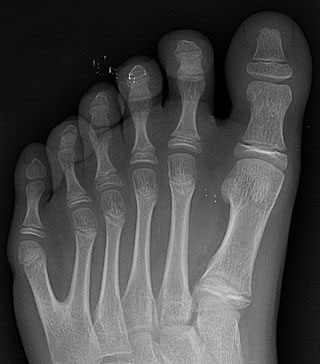

Kuudes varvas toi pueblointiaanille mainetta ja kunniaa

Tekijä Kalmistopiiri22.8.201619.2.2020